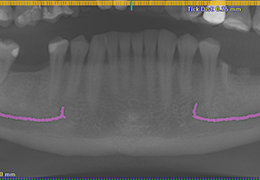

ANYTHINK 经导管主动脉瓣膜置换术分析系统